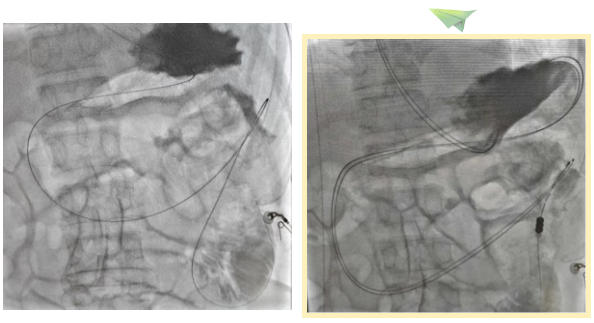

近日,北医三院秦皇岛医院肿瘤科白利君主任带领团队医生,成功为一名消化道穿孔并发十二指肠-结肠瘘的老年危重患者实施X线造影下鼻空肠营养管置入术,精准建立起关键的肠内营养支持通路,为患者的后续治疗与康复奠定了坚实基础。这一技术的成功应用彰显了医院以患者为中心,致力于提供高质量医疗服务的专业实力与责任担当。

孙阿姨因“消化道穿孔2月余,腹痛加重7天”入院,病情迅速进展为感染性休克,随即转入重症医学科接受紧急救治。全面检查后,医生发现其存在十二指肠-结肠瘘,这一严重并发症导致胃肠道功能严重受损,孙阿姨完全无法经口进食,营养支持成为维持生命与战胜疾病的当务之急。面对复杂病情,白利君主任团队进行了充分的评估与审慎的研讨,决定采用X线造影下鼻空肠营养管置入术,为孙阿姨开辟一条安全、有效的肠内营养通道,为后续的综合治疗创造有利条件。

鼻空肠营养管置入术是一种经鼻腔插入导管直达空肠的微创治疗技术。在此次手术中,北医三院秦皇岛医院的医疗团队巧妙运用X线造影技术,为手术的精确性与安全性提供了坚实保障。手术过程中,医生在X线实时动态影像的精准引导下,将细小的营养导管通过患者的鼻腔、食道,一步步精确送达空肠指定部位。这种动态可视化操作,使得医生能够随时观察并调整导管位置,确保其准确无误地进入目标区域,最大限度地降低了操作风险,保障了患者的安全。